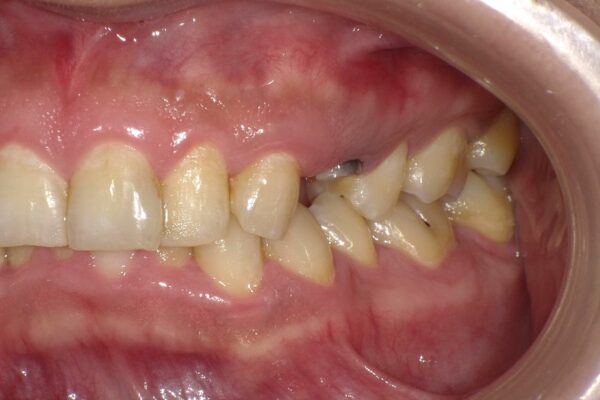

Images